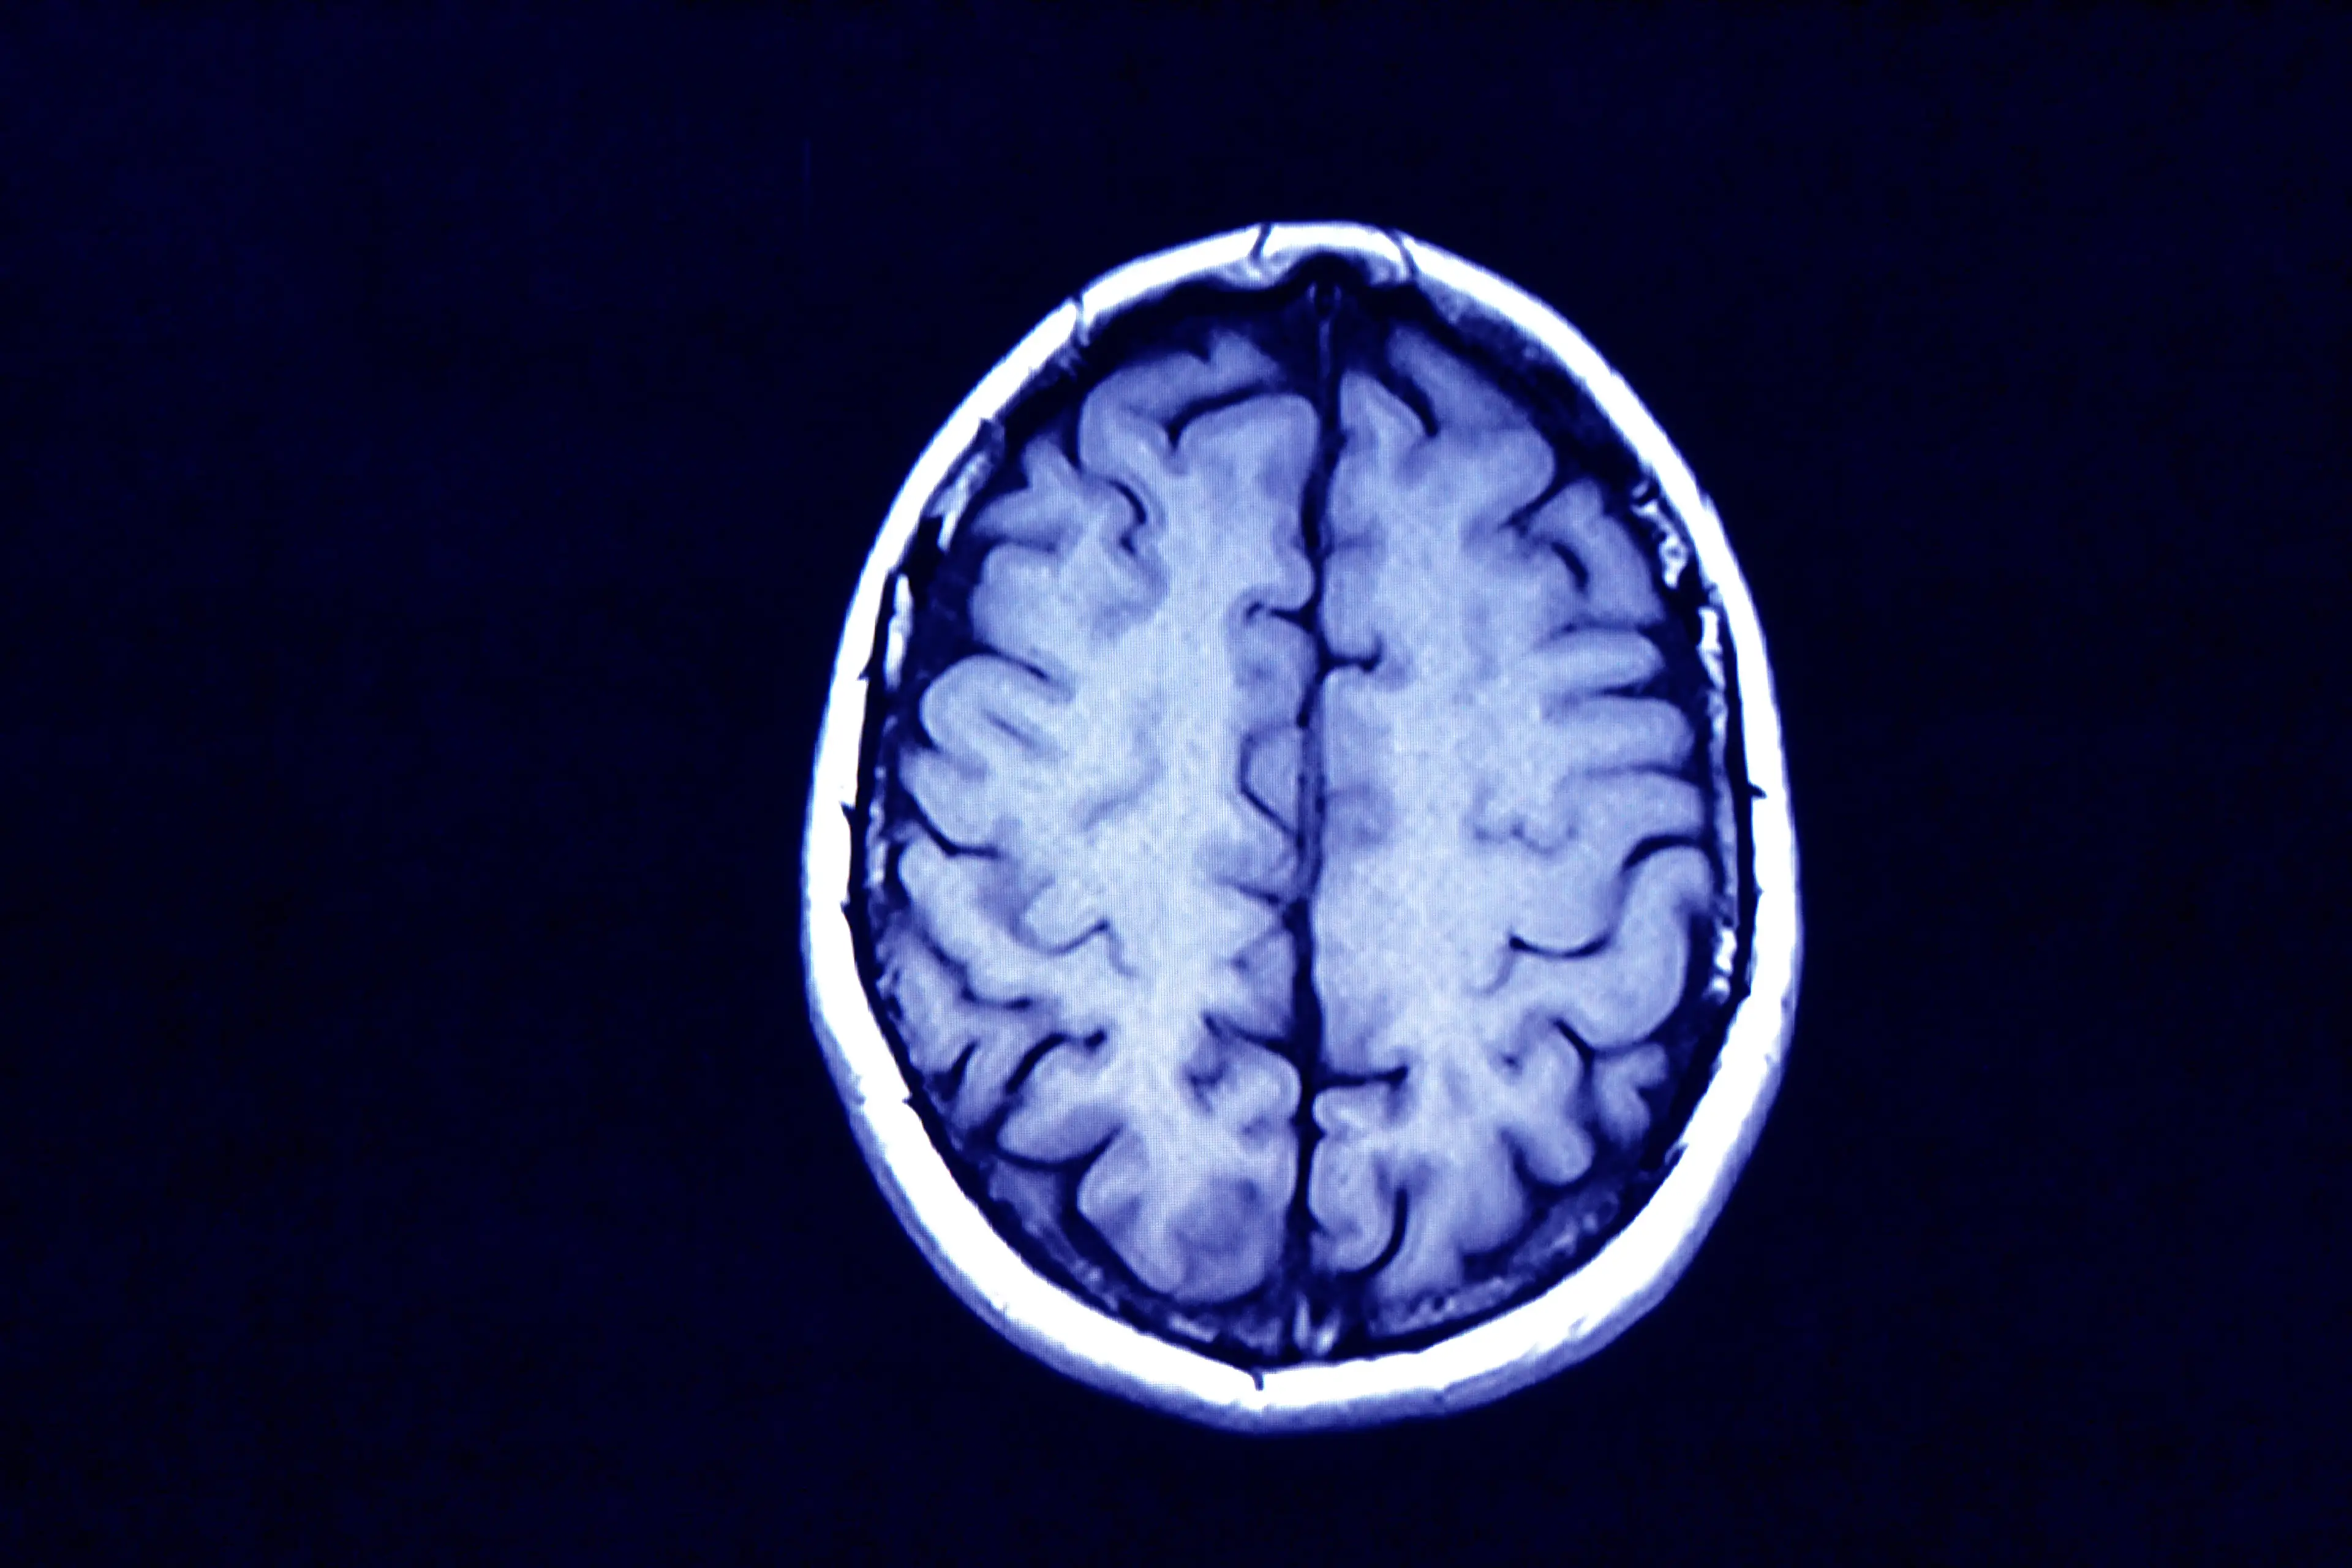

A medical expert has highlighted the one thing people should introduce into their routine after witnessing something seriously ‘concerning’ within her patients’ brains.

“They truly don’t make the connection that their weakness is due to their lack of muscle movement, and they definitely are unaware of the impact that it might be having on their brain,” she explained in a new interview with Self.

Explaining her reasoning, the practitioner said: “Every time you exercise, you secrete nerve growth factor, a peptide involved in regulating neurons in the brain.

“It can also support myelin, the neuroprotective sheath that helps nerve fibres shuttle electrical impulses quickly and efficiently and can degenerate with age.”